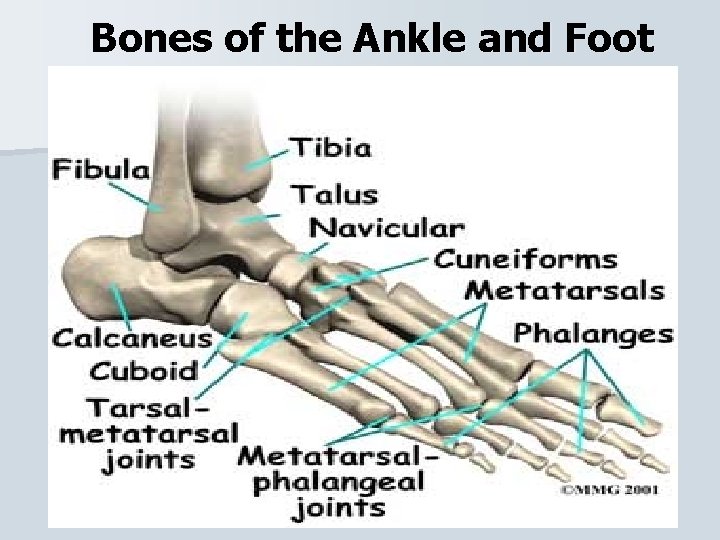

Bones of the Ankle and Foot